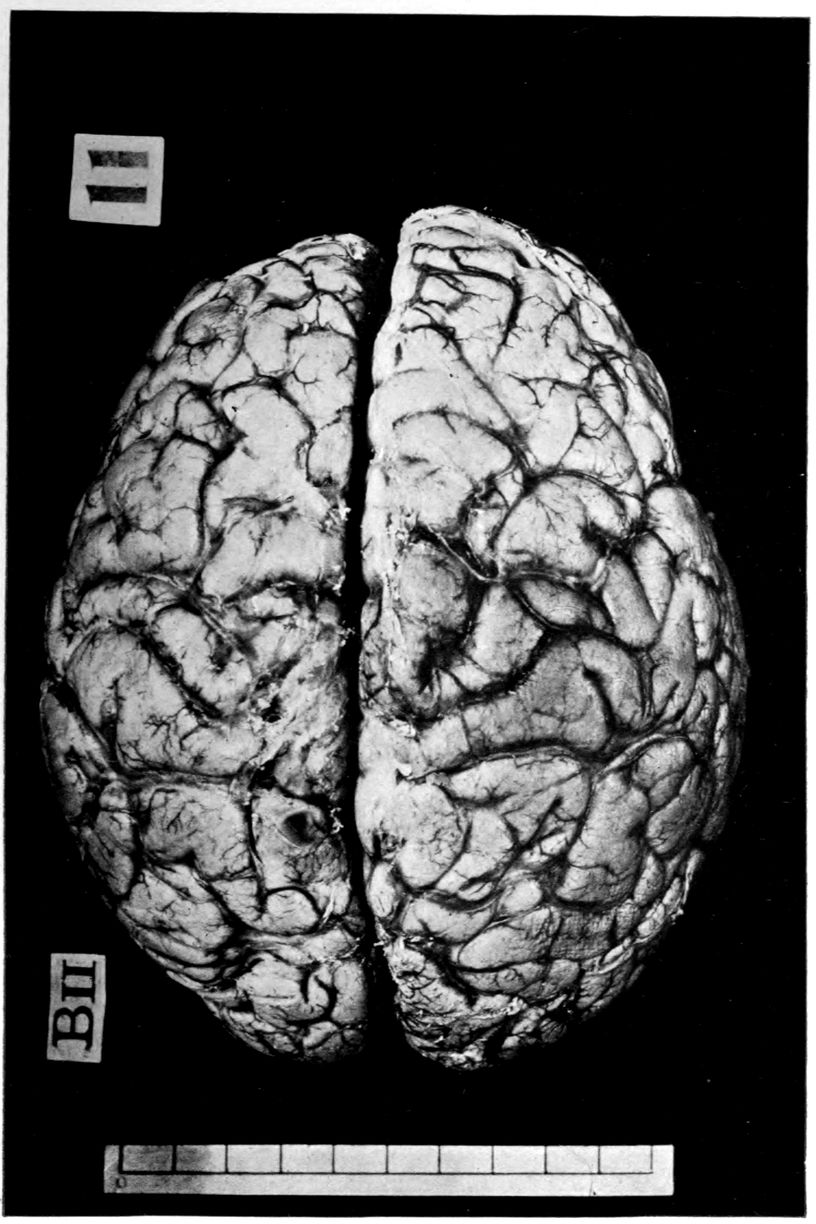

VASCULAR NEUROSYPHILIS (“syphilitic cerebral thrombosis”). Autopsy.

Case 4. James Pierce was an almshouse transfer to the Danvers Hospital in his fiftieth year. He died three years later. The accompanying brain pictures demonstrate so extensive a lesion of the left hemisphere that it is of great interest to determine if possible the genesis and course of his disease. It appears that syphilis had been acquired somewhere about the age of 38 or 40, so that the total duration of the process was between 13 and 15 years. In Pierce’s forty-third or forty-fourth year, he had a shock while walking in the streets of his native city, whereupon he was subsequently transferred to the Danvers Hospital, whose data have been summed up as follows (we are obliged to Dr. Charles T. Ryder for these data):

Neurological examination: Neuromuscular condition: Barely able to walk or stand without assistance; hemiplegia of right side; swings foot out and drags toe out and around in attempting to walk. Right hand held by side, flexed at right angle; fingers contracted and thumb thrown across palm. Can lift arm from side; practically no movements of forearms or fingers; atrophy of deltoid, arm, forearm, and hand. Muscular movements of left upper extremities fairly well performed; good strength.

Cranial nerves: Refuses to respond to any tests to determine hearing or vision, but evidently hears what is said to him, and in his movements gives no evidence of deafness. Right corner of mouth droops; tongue protrudes straight.

Reflexes: Pupils dilated; margins irregular; left pupil larger; they vary in size but it is impossible to determine whether the variation is due to light or accommodation reflex. Reflexes of right side extremely exaggerated throughout; there is little ankle clonus; Babinski is not obtained, patient holding his toes in flexed position in resisting attempts to elicit reflexes.

43Sensations: Reaction to pain stimuli on either side. Evidently some anesthesia on right side, but pressure is apparently very painful. There is considerable spasticity of limbs on right side on passive motion. Too demented to make accurate tests.

The above examination was made on May 6, 1904. On May 20th the record states:

There is almost complete sensory aphasia with word-deafness; some paraphasic circumlocution. Many of his words are very well enunciated but have no meaning. Is apparently unable to recognize objects or their uses.

Brother stated that he was always supposed not to be over bright. Physician’s certificate states that he is epileptic, averaging two attacks per week. On the 15th of May he had a general convulsion; was unconscious for half an hour, and dull and drowsy for two hours afterwards. On the 19th, he had a similar attack in the afternoon, the convulsion lasting a minute, and he was stuporous for an hour.

On November 8th he had a severe epileptic convulsion. His body was curled up to the right. The convulsive seizure lasted for two minutes and was followed by complete unconsciousness for an hour, when the patient roused and appeared as usual in a few minutes. From that time to December 15th he had five epileptic convulsions; he was much more feeble, and unable to help himself as much as formerly.

Nov. 7, 1905: Patient has had occasional convulsions since last note, but none during the last three months. He is confined to bed, has become very much demented, and shows very marked speech defect, so that he is almost unintelligible. He understands only the simplest directions. Legs are considerably contracted and knees are flexed. Arm and hand on the right are paralyzed and show some atrophic changes; partially flexed. Left elbow jerk is very lively. On May 23, 1906 he was reported as having Achilles on right side only, and Babinski on right side. He died January 5, 1907.

The autopsy findings were as follows:

Head: Calvarium of moderate thickness; diploë present; dura slightly adherent over bregmatic region. Longitudinal sinus contains cruor clot. Dura is somewhat thickened and slightly more opaque than normal. Pacchionian granulations, small but fairly numerous. Pia contains throughout a considerable excess of clear 44serous fluid. The convolutions in general are of good breadth and proportion. There is an atrophic area roughly circular in outline and about 2 cm. in diameter in the posterior part of the right third frontal convolution corresponding to Broca’s area on the opposite hemisphere. The space thus formed is filled with edema held by the pia. On the left side is a similar subpial collection which covers the site of the posterior portions of all of the third frontal convolutions, parts of the lower end of the precentral convolution, and the whole of the first temporal convolution, which have disappeared entirely. The basal vessels show slight changes.

Cerebellum and basal ganglia are grossly normal.

The spinal membranes are negative. The regions of the pyramidal tracts in the cord are firm, project slightly from surface of section, and are china white.

Summary: Here is a picture made up almost purely of Vascular Neurosyphilis, with Secondary Spinal (Pyramidal Tract) Changes. Doubtless the genesis of this picture is allied to that of Case 1 (Alice Morton) and to that of the terminal vascular complications in a tabetic, Case 2 (Francis Garfield).

The absence of meningeal and parenchymatous (i.e., outside the region of necrosis produced by the vascular disease) lesions is characteristic of an important group of neurosyphilitic diseases. It is clear that the case, although one of extensive lesions, is not one of diffuse lesions in the sense of Case 1 (Alice Morton).

The spinal fluid picture in life may nevertheless show (as other cases amply demonstrate) a certain amount of lymphocytosis and possibly plasmocytosis, together with a variety of other changes. Treatment might be expected to keep down these associated changes, although obviously the effects of the necrosis are final and definite. Franz in Washington has succeeded in “reeducating” some of these hemiplegics, employing lower mechanisms of the nervous system.

Vascular neurosyphilis—effects of syphilitic thrombosis of Sylvian artery 10 years before death. (Case 4.)

Case 4. (See previous figure for brain lesion.) Three levels of the spinal cord showing unilateral pyramidal tract sclerosis, 10 years after cerebral thrombosis.